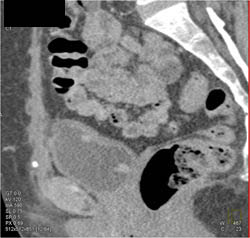

Cystogram S/P Prostate Resection